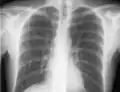

If a pneumothorax is suspected, an upright chest x-ray should be obtained. An upright chest x-ray is preferred because free air will migrate to the apex of the lung, where it is easily visualized. Of course, this is not always possible, particularly in critically ill patients in the intensive care unit. Radiographs obtained in the supine position fail to detect 25–50% of pneumothoraces.[6] Instead, bedside ultrasound is a superior method of detection in those too ill to obtain upright imaging.[3]

During subclavian vein central line placement, the catheter can be accidentally pushed into the internal jugular vein on the same side instead of the superior vena cava. A chest x-ray is performed after insertion to rule out this possibility.[25] The tip of the catheter can also be misdirected into the contralateral (opposite side) subclavian vein in the neck, rather than into the superior vena cava.

The line is then inserted using the Seldinger technique: a blunt guidewire is passed through the needle, then the needle is removed. A dilating device may be passed over the guidewire to expand the tract. Finally, the central line itself is then passed over the guidewire, which is then removed. All the lumens of the line are aspirated (to ensure that they are all positioned inside the vein) and flushed with either saline or heparin.[1] A chest X-ray may be performed afterwards to confirm that the line is positioned inside the superior vena cava and no pneumothorax was caused inadvertently. On anteroposterior X-rays, a catheter tip between 55 and 29 mm below the level of the carina is regarded as acceptable placement.[36] Electromagnetic tracking can be used to verify tip placement and provide guidance during insertion, obviating the need for the X-ray afterwards.